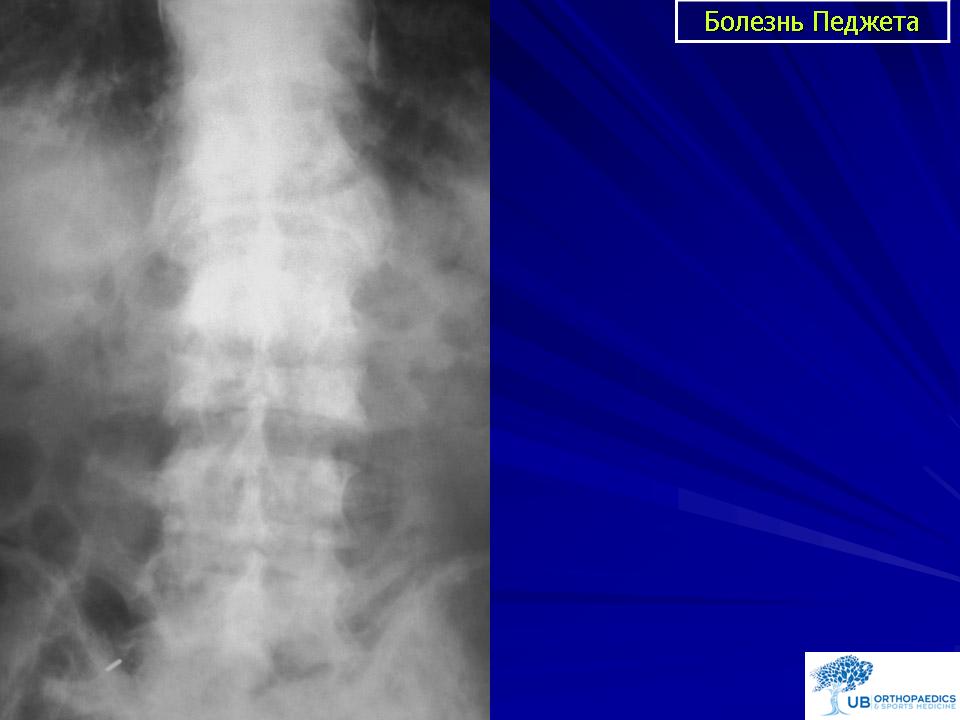

Рентгеновские снимки и визуализация болезни Педжета

Раздел: Мудрость в объективе